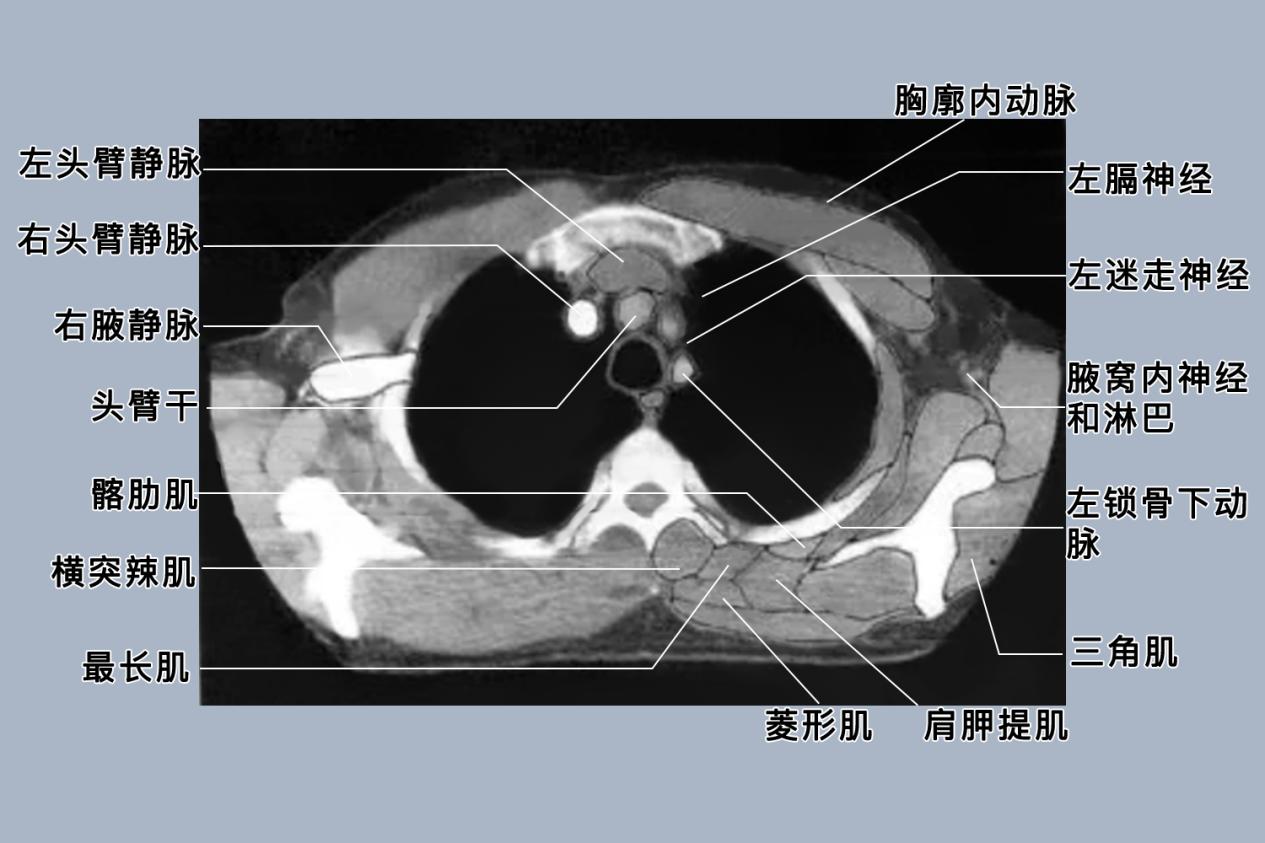

胸部的组织结构复杂,由于各组织的密度不同,差异很大,其CT值的范围广,因此在观察胸部CT时,至少需采用两种不同的窗宽和窗位,分别观察肺野与纵隔,有时还需采用骨窗。

胸部CT正常表现为两肺支气管血管束未见增多、增粗及紊乱;两肺未见异常密度影;纵隔内未见异常增大的淋巴结;气管、左右主支气管显示通畅;两侧胸膜未见增厚、粘连。心脏及大血管位置如常,未见异常扩张及狭窄,胸廓各组成骨骨质密度正常。